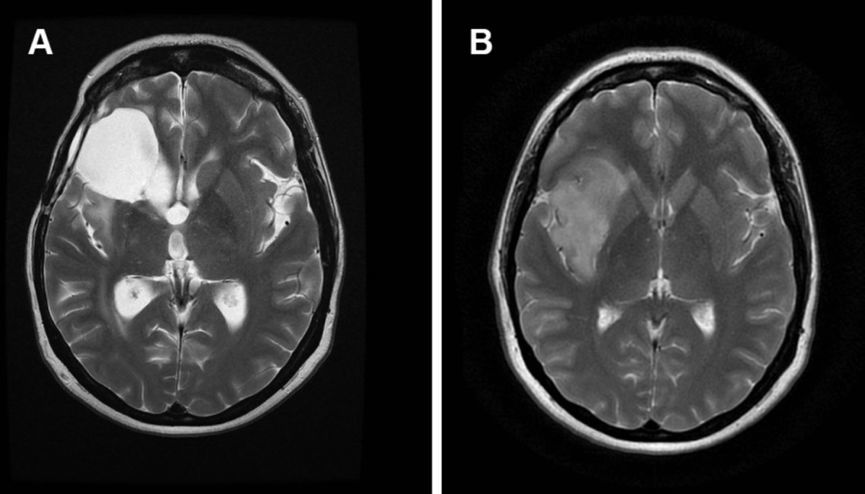

脑瘤有良恶性之分,恶性发展快,病程短,神经系统症状逐渐出现,并且进行性加重,带瘤存活 20 余年的可能性微乎其微。

良性发展慢,病程长,患者可以没任何症状,也可以随着肿瘤生长,影响到脑部血液循环,阻塞脑脊液的循环通路,造成颅内积水或脑水肿,甚至会发生脑疝,危及生命。

虽然良性肿瘤存活期可能大于 20 年,但症状应进行性加重,不会以反复发作、不残留神经功能障碍为表现。

脑膜瘤